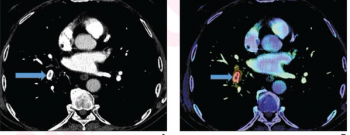

In a new study involving over 11,700 chest computed tomography (CT) scans in oncology patients, adjunctive artificial intelligence software demonstrated a sensitivity rate of 91.6 percent for incidental pulmonary embolism (IPE) and reduced median detection and notification time for IPE-positive scans from multiple days to one hour for a radiology department at a comprehensive cancer center.